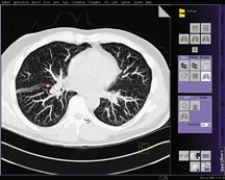

CAD for Lung Creates Consistency

Since CAD does in fact produce false positive rates and has shown to be inferior in detecting very small lesions, the FDA requires that CAD software only function as a second reader.

“I agree with that utilization [directed by the FDA] because it ensures that a human interpreter is in the loop,” said Joseph Schoepf, M.D., associate professor of Radiology and Medicine at the Medical University of South Carolina, who uses Siemen’s syngo Lung CAD with syngo LungCARE CT. “The reader evaluates the lungs for findings that he may have missed and discards false positives. Ideally, a CAD system would improve accuracy and speed up the review. However, while CAD as a second reader improves accuracy, it requires additional time to evaluate potential new findings. Therefore, it is important that any CAD system be sensitive without increasing the number of false positives. In my experience I have noticed that CAD has a good sensitivity and yields an average of two false positives per case, if there is no additional diffuse lung disease.”

Although CAD increases the number of false positives slightly, Dr. Schoepf is able to easily review and discard false positives.

“I’d rather shoot for sensitivity than specificity because it is very easy to discard a false positive,” he said. “It’s more of a problem when you have an evident lesion missed by the computer. Discarding false positives takes about a split second and a click of a button.”

Another consideration is the false negative rate, which may pose even more of a dilemma for radiologists. Dr. Schoepf evaluated the specificity performance of CAD in a study consisting of 100 chest CT cases that were read as normal in the clinical read-out. CAD tools then reevaluated the findings and found a total of five lesions greater than 1 cm that were missed. “While a 1 cm lesion is fairly large by today’s standards, this can happen if you are extremely busy and distracted,” indicated Dr. Schoepf. “The computer interprets data consistently – not like a human. I see CAD tools as introducing an element of consistency to human interpretation. In fact, such tools do not get distracted or fatigued like a human.”

Computers may not face human limitations, but according to David Mendelson, M.D., associate professor of Radiology at Mt. Sinai School of Medicine, “people don’t see everything; nor does CAD. It misses things in that 4-10 mm range. It’s not a perfect device, but it has to be understood in the context of development.”

While it may miss some lesions, it can also detect lesions missed by the radiologist. “Every now and then it finds nodules that I had not called spontaneously – 4-5 mm sized nodules. It has not picked up anything that is a carcinoma that we missed, but on the other hand, I would not let you take this away from me. I still believe that even if you are in the lung nodule detection business, you’d want to be accurate. As long as this is available at a fair price, I believe we owe it to our patients to do this.”

Dr. Mendelson, who uses Hologic/R2’s ImageChecker CT Lung CAD tool, believes CAD “can be incorporated very easily into your routine. Some may think it’s a concern that it adds time. The right way is to read it yourself, then look at the results of ImageChecker. I’ve got that down that it adds about a minute. It’s an added service and easily integrated into the workflow without the burden of time, and it makes a better radiologist.”